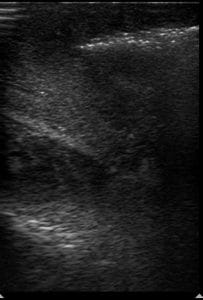

A 62-year-old male with no reported past medical history presented with worsening left foot swelling after cutting his toenail. Abnormal vital signs included a blood pressure of 166/99 mmHg, heart rate of 121 beats per minute, and a fingerstick blood glucose of 500 mg/dL. On physical examination, his left foot was swollen, warm, erythematous, and tender to palpation. There was a poorly healing wound on the plantar surface of his left foot. Of note, crepitus was not felt. A point-of-care ultrasound (POCUS) of the left foot was performed which showed extensive cobblestoning without a discrete fluid collection, and deeper “dirty” shadowing suggestive of subcutaneous air (Figure 1). When gentle pressure was applied with the transducer, the subcutaneous air mobilized, confirming our suspicion that the “dirty” shadowing visualized was indeed subcutaneous air (Video S1). We call this novel sonographic finding “sonographic crepitus.” This dynamic visualization of subcutaneous air movement with transducer pressure application ultimately raised our suspicion for necrotizing fasciitis, in an otherwise equivocal physical examination of the wound. Prior studies have described sonographic findings consistent with necrotizing fasciitis such as subcutaneous thickening, air, and fascial fluid as well as an approach to early POCUS screening in these patients [2,3]. We hope that sonographic crepitus may be added to the continuum of sonographic findings associated with necrotizing fasciitis and further assist diagnosis in ambiguous cases.

Figure 1. Cobblestoning and hyperechoic subcutaneous air with “dirty” shadowing, suggestive of necrotizing fasciitis.